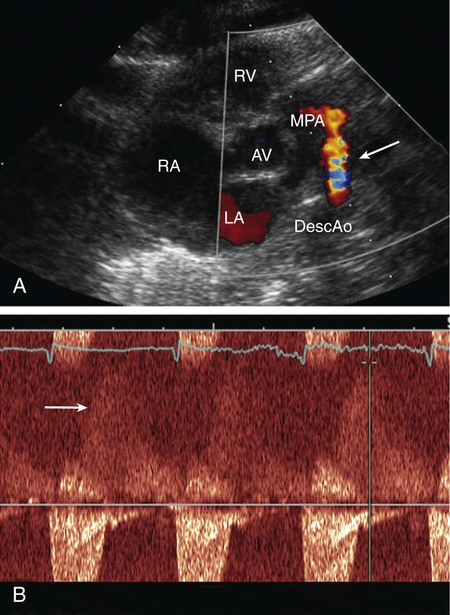

On echocardiogram, the cardiac chambers will be normal in size if the ductus is small. With large shunts, left atrial and left ventricular dimensions are increased. The ductus can easily be visualized directly and its size estimated. Color and pulsed Doppler examinations demonstrate systolic or diastolic (or both) retrograde turbulent flow in the pulmonary artery, and aortic retrograde flow in diastole (Fig. 426-10) in the presence of a large shunt.

The clinical signs and echocardiographic findings are sufficiently distinctive to allow an accurate diagnosis by noninvasive methods in most patients. In rare patients with atypical findings, cardiac catheterization may be indicated for confirmation of diagnosis. Cardiac catheterization will demonstrate either normal or increased pressure in the right ventricle and pulmonary artery, depending on the size of the ductus. The presence of oxygenated blood shunting into the pulmonary artery confirms the left-to-right shunt. The catheter may pass from the pulmonary artery through the ductus into the descending aorta. Injection of contrast medium into the ascending aorta shows opacification of the pulmonary artery from the aorta and identifies the ductus.